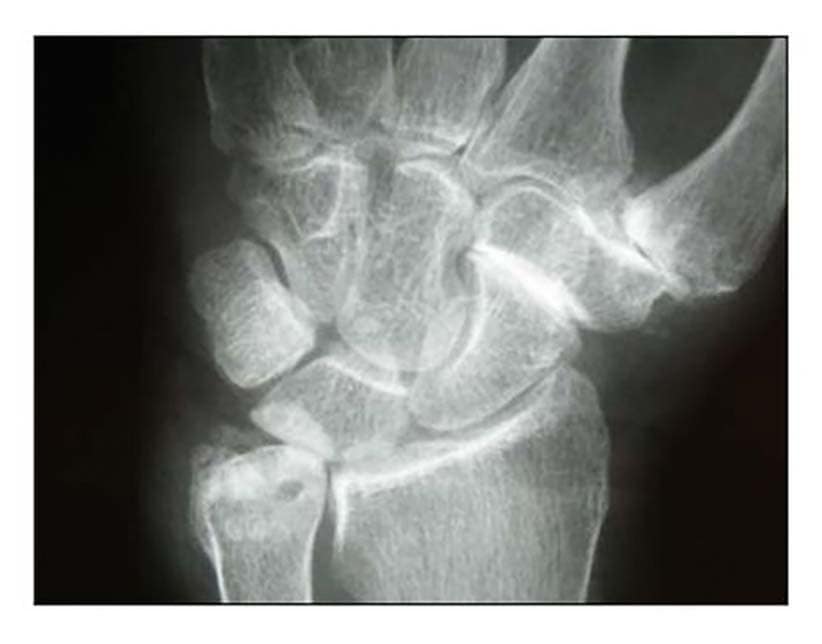

Die Rhizarthrose gehört zum rheumatischen Formenkreis und macht sich je nach Stadium durch eine sehr schmerzhafte zunehmende arthrotische Zerstörung des Daumensattelgelenkes bemerkbar. Nach einer Untersuchung von Pellegrini 1 erkranken Frauen 10- bis 15-mal häufiger an Rhizarthrose als Männer. Das deckt sich mit den Erfahrungen des Autors aus den Evaluierungsübersichten von fast 4.000 Patientinnen und Patienten mit dem durchschnittlichen Verhältnis von 13:1 zugunsten der Patientinnen. Die Rhizarthrose tritt bei Frauen nach den Erfahrungen des Autors ca. 3 Jahre nach dem Beginn der Menopause auf und ist vermutlich genetisch bedingt: Nur zwei Prozent der Patientinnen des Autors erwähnten in der Anamnese, keine Schwangerschaft gehabt zu haben. Auslöser für die Rhizarthrose bei Männern ist in den meisten Fällen eine traumatisch bedingte Verletzung des Daumensattelgelenkes („Skidaumen“) oder eine ständige berufliche Überbeanspruchung, zum Beispiel bei Vibrationen durch Maschinen oder auch durch handschriftliches Schreiben in Büroberufen. Die Rhizarthrose tritt nach Eaton/Littler radiologisch klassifiziert in vier Stadien auf (Abb. 1) 2:

- Stadium I: normale Gelenkkonturen, erweiterter Gelenkspalt (Erguss)

- Stadium II: geringe Gelenkspaltverschmälerung, evtl. vorhandene Gelenktrümmer kleiner als 2 mm

- Stadium III: sklerotische und zystische Veränderungen im subchondralen Knochen, Osteophyten größer als 2 mm, Zerstörung des Daumensattelgelenkes, normale trapezioskaphoidale Gelenkfläche

- Stadium IV: zusätzlich zum Verschleiß der trapeziometakarpalen Gelenkfläche degenerative Veränderungen im Bereich der trapezioskaphoidalen Gelenkfläche